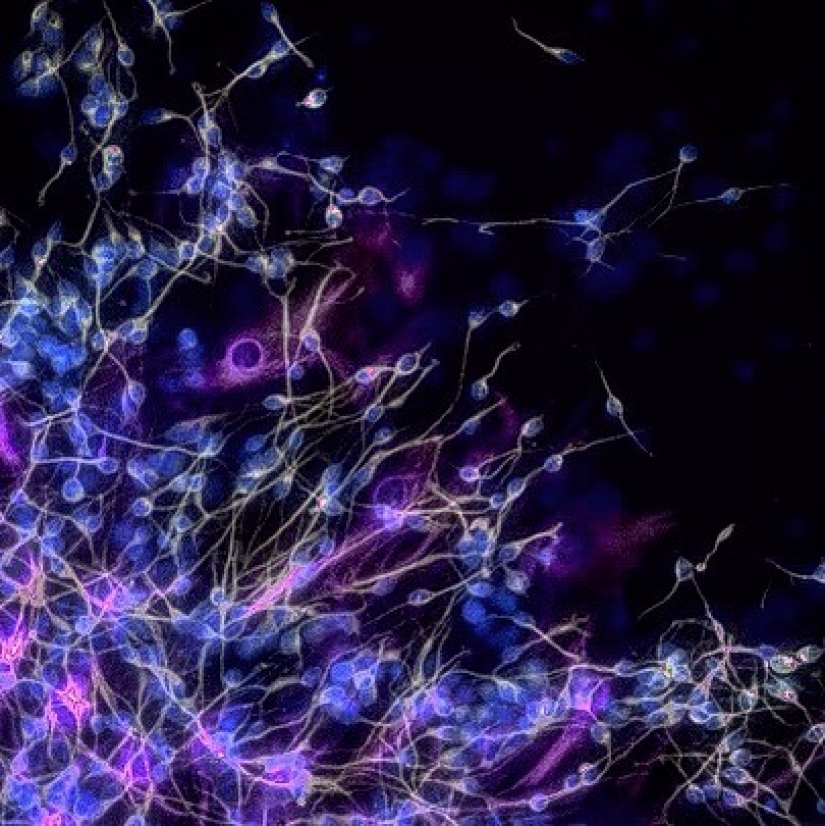

Just imagine, all our memories are the product of this cluster of cells.